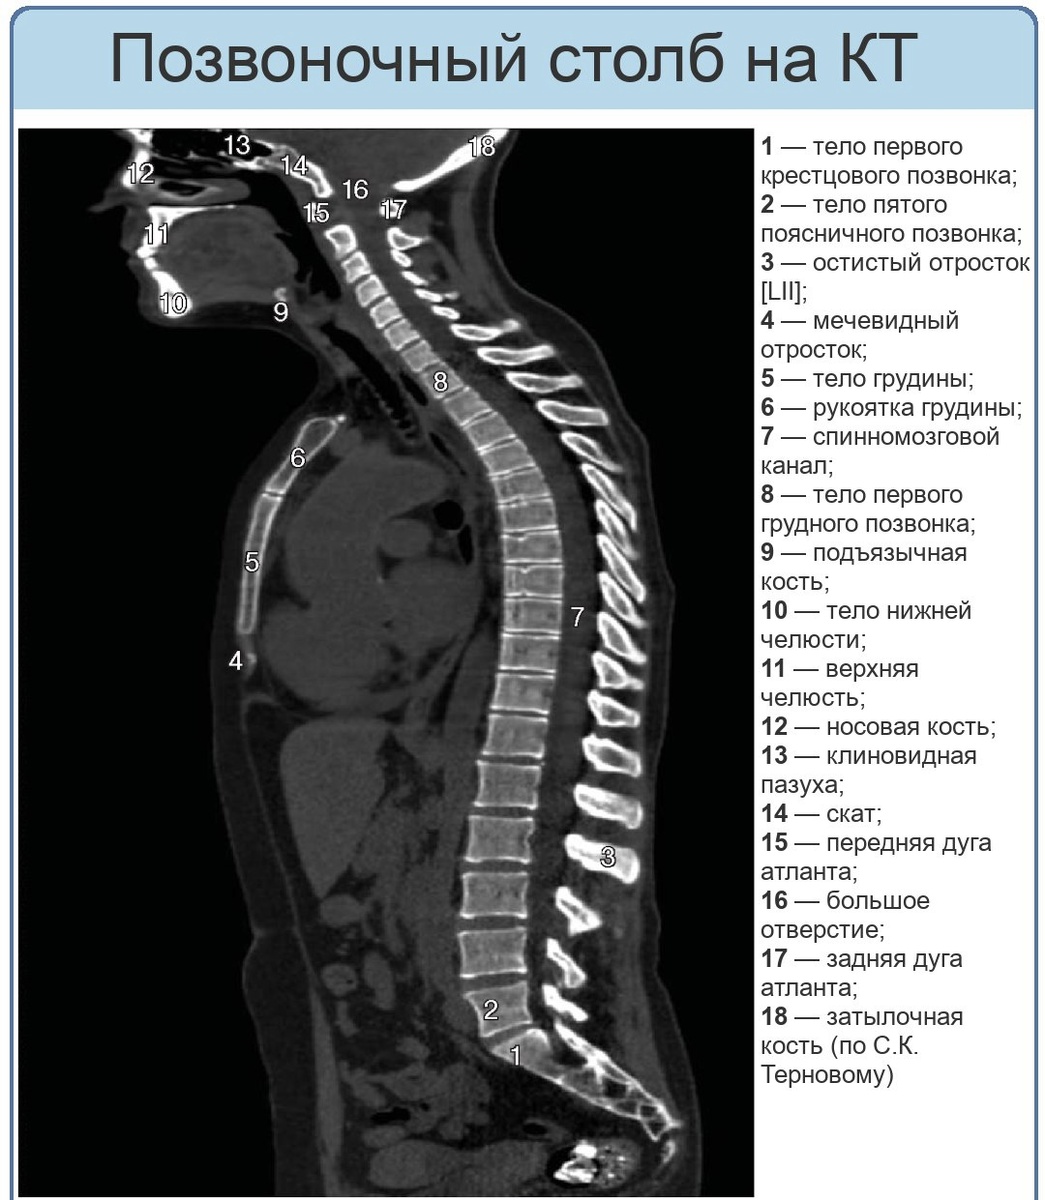

Позвоночный столб, или позвоночник (лат. columna vertebralis)– это основная часть осевого скелета человека, состоящая из 32-34 позвонков, последовательно соединенных друг с другом.  Функции позвоночного столба:  Опорная: Двигательная: Защитная: Амортизационная: Строение позвоночника:  Позвонки: Межпозвоночные диски: Отделы позвоночника: Шейные позвонки (vertebrae cervicales)- -это семь верхних позвонков позвоночника, расположенных в области шеи, непосредственно под черепом. Они отвечают за поддержку и движение головы, а также за защиту спинного мозга, проходящего в позвоночном канале.  Два верхних шейных позвонка - Атлант (Atlas) и Аксис (Axis), имеют анатомическое строение, отличное от строения всех остальных позвонков. Благодаря наличию этих позвонков, человек может совершать разнообразные повороты и наклоны головы. Первый позвонок называется «атлант» (по имени титана из древнегреческих мифов, удерживающего на своих плечах небесный свод). Он неподвижно сросся с черепом. Ат

Позвоночный столб, или позвоночник (лат. columna vertebralis)– это основная часть осевого скелета человека, состоящая из 32-34 позвонков, последовательно соединенных друг с другом.

Отделы позвоночника:

• Шейный: Состоит из 7 позвонков, включая атлант и эпистрофей.

• Грудной: Состоит из 12 позвонков, к которым крепятся ребра.

• Поясничный: Состоит из 5 позвонков.

• Крестцовый: Состоит из 5 сросшихся позвонков, образующих крестец.

• Копчиковый: Состоит из 3-5 сросшихся позвонков, образующих копчик.